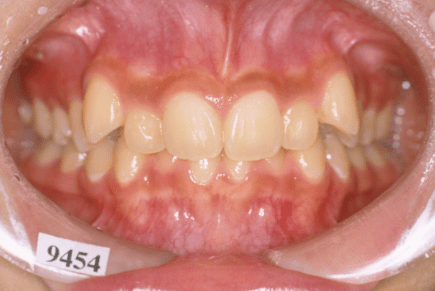

叢生とは、歯並びがデコボコの状態のことを指します。

叢生(デコボコ)

原因:歯の大きさと顎の骨の横幅のアンバランス